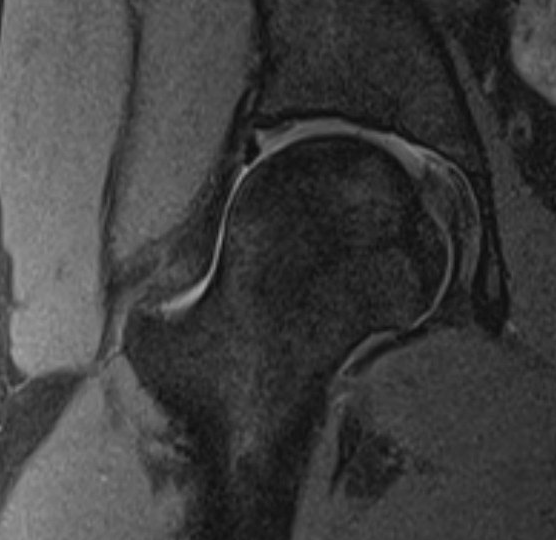

MRI

Labral tears

Best seen on coronal MRI

Saied et al BMC Musculoskeletal Disorders 2017

- systematic review

- labral tears: MRI sensitivity 86% and specificity 83%

- chondral lesions: MRI sensitivity 87% and specificity 72%

- labral tears: MRA sensitivity 91% and specificity 58%

- chondral lesions: MRA sensitivity 75% and specificity 79%